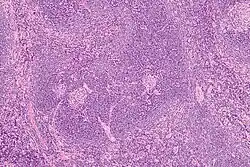

![]() Histology of a normal secondary lymphoid follicle, with yellow arrows pointing at the mantle zone. | |

The mantle zone (or just mantle) of a lymphatic nodule (or lymphatic follicle) is an outer ring of small lymphocytes surrounding a germinal center.[1]

It is also known as the "corona".[2]

It is the location of the lymphoma in mantle cell lymphoma.

Mantle zone expansion may be seen in benign, such as Castleman disease, and malignancy, i.e., Mantle cell lymphoma. Tcl-1 is expressed in the mantle zone.